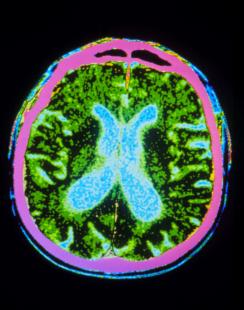

Comment agir dès la phase présymptomatique, avant les symptômes moteurs ? « La maladie de Parkinson évolue par stades. Les dépôts de synucléine débutent à la phase prémotrice dans la profondeur du tronc cérébral, puis s'étendent à la phase motrice au mésencéphale dans le locus niger avant de diffuser dans le cortex. En agissant aux stades moteurs, on agit en milieu de tableau », précise le Pr Azulay. À la phase prémotrice, des troubles du comportement en sommeil paradoxal dits « RBD » (Rem-sleep Behavior Disorder), rêves très agités au vécu souvent angoissant avec abolition de la baisse normale de tonus, seraient associés à un risque élevé de développer une synucléopathie à 10 ans. L'équipe du Pr Marie Vidailhet cherche dans l'étude ICEBERG à identifier sur 300 patients des marqueurs permettant de prédire et de suivre la progression de la maladie. « L'association de RBD, d'une hyposmie et d'une imagerie fonctionnelle cérébrale évocatrice, au Dat-TDM ou au PET-TDM à la fluoro dopa, traduirait un risque combiné de 90 % », avance le Pr Azulay.